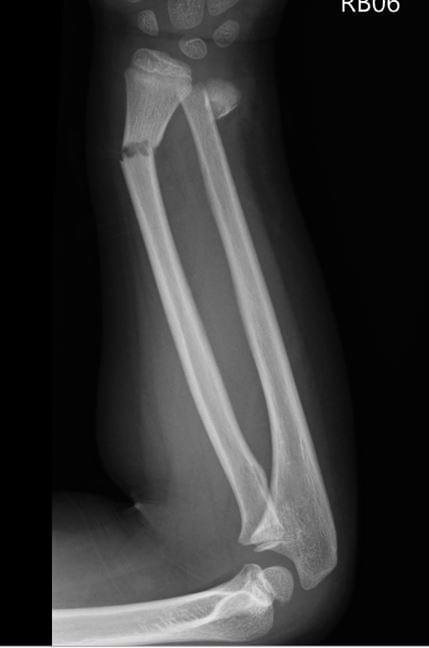

Radial or ulna shaft fracture or deformity

- 除非年紀很小,發生在shaft及靠近手肘的骨折,不要太期望會remodeling.

- 如果interosseous space狹窄,至少要進行closed reduction and casting. 如果復位不好,就進開刀房reduction.

- Long arm cast需要cast index: 0.8。一定要跟家長告知compartment syndrome風險